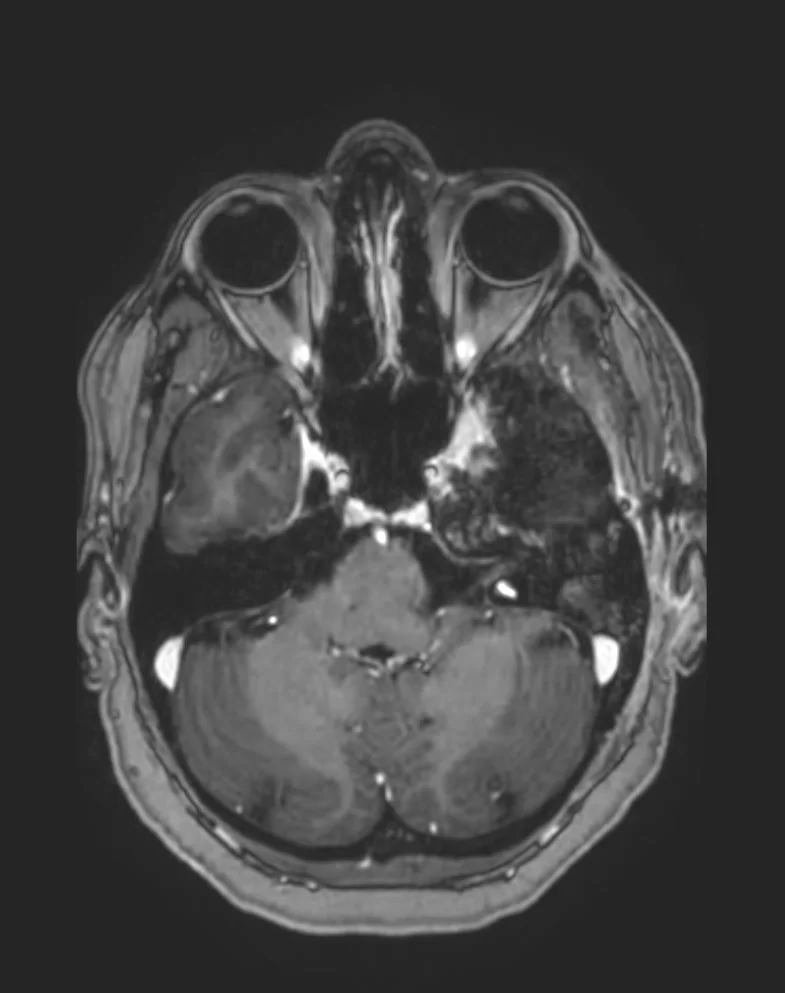

Η μαγνητική τομογραφία εγκεφάλου ανέδειξε χωροκατακτητική εξεργασία στην περιοχή του τριδύμου νεύρου αριστερά.

Η μετεγχειρητική μαγνητική τομογραφία εγκεφάλου δείχνει ένα εξαιρετικό αποτέλεσμα, με πλήρη αφαίρεση της βλάβης.